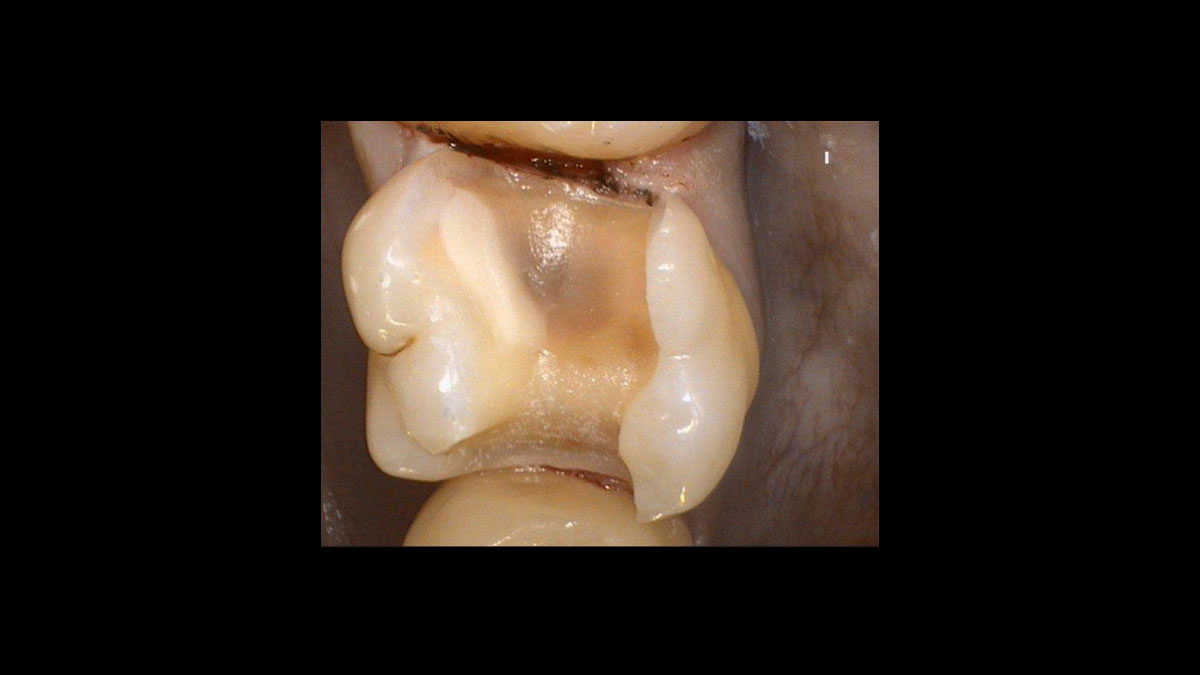

Cirugía

• Cirugía

• Gingivectomía

• Gingivoplastia